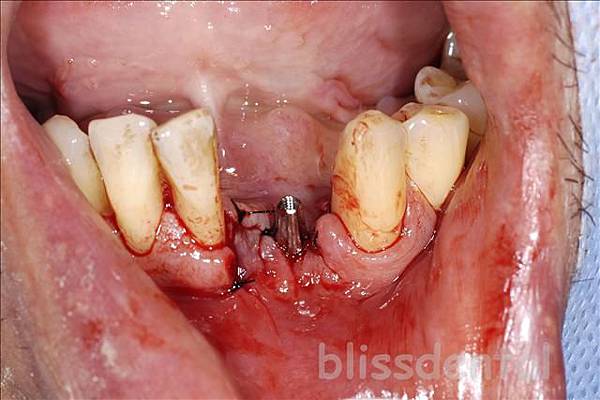

植牙分享, 黃偉哲醫師部落格下顎門牙嚴重牙周病,拔除後立即植牙 Posted on 2009-10-192019-06-10 by blissdental 患者左下顎二顆門牙因為嚴重牙周病的關係搖搖欲墜 有關植牙 經過討論後決定拔除之後植牙,並馬上以臨時假牙解決美觀問題 上圖為患者全口x光,可以看到左下門牙與側門牙因為嚴重牙周病骨質破壞嚴重左下側門牙”懸浮”在牙肉上 先經過第一階段牙周治療解決發炎的問題之後進行拔牙與植牙術式。術前口內照片 拔除無救牙後,清除肉芽組織 植體植入 術後x光 臨時假牙 永久假牙 分享給您的朋友 有關蛀牙 上顎側門牙根管治療不完全導致根尖病變